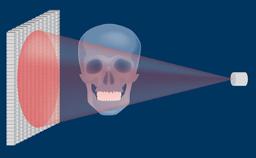

A implantodontia evoluiu consideravelmente desde os protocolos de tratamento precoce, nos quais o posicionamento dos implantes não era considerado crítico para um resultado bem-sucedido. Nesta abordagem orientada cirurgicamente, os implantes foram instalados onde havia osso suficiente para apoiá-los, e a ênfase estava no resultado funcional. Esta imagem clínica mostra três implantes adjacentes suportados por coroas unitárias. Isso proporcionou ao paciente um bom resultado funcional, mas a estética ao nível da emergência do implante foi apenas uma consideração secundária. Na implantodontia moderna, o resultado estético geral é de igual ou maior importância para o paciente. Os resultados estéticos estão intimamente relacionados a um alto nível de precisão no posicionamento dos implantes dentários de suporte. Uma segunda imagem clínica mostra um exemplo de uma coroa unitária implantossuportada no incisivo central superior esquerdo, onde o posicionamento cuidadoso do implante permitiu que o perfil de emergência imitasse o do incisivo central natural. Guias de transferência para orientar a instalação precisa tridimensional do implante são críticos para alcançar esse resultado. Este Módulo de Aprendizado ITI discutirá o uso rotineiro de guias de transferência na implantodontia.